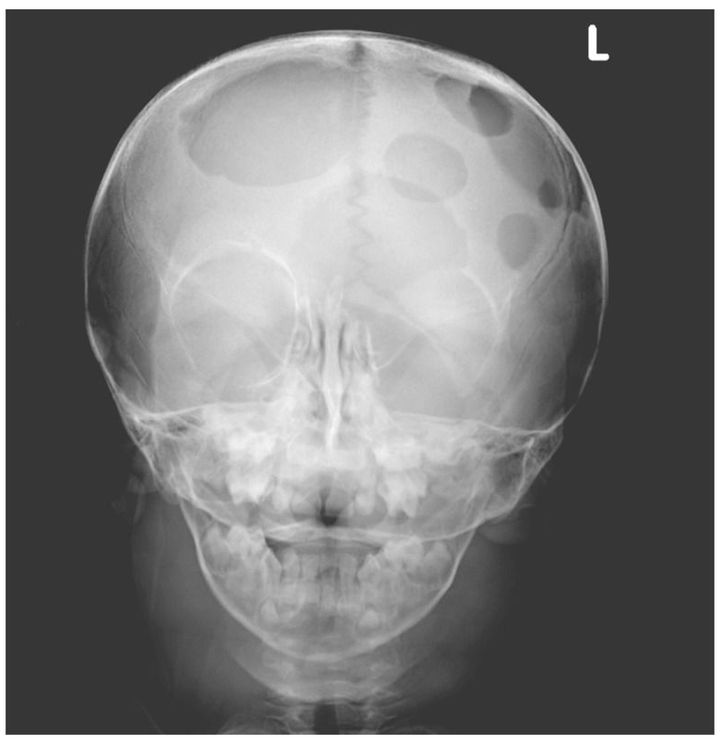

A 2-year-old boy presented with a 1-year history of refractory eczema and a 4-week history of enlarging neck masses. On physical examination, his weight and height were below the fifth percentile for his age. He had bilateral proptosis, serous discharge from both ears, and extensive rash on the scalp, chest, and upper back, along with palpable defects in the skull and bilateral posterior cervical, submandibular, and supraclavicular lymphadenopathy. The patient did not have hepatosplenomegaly or diabetes insipidus at diagnosis. Laboratory testing revealed anemia of chronic disease, with a hemoglobin level of 6.6 g per deciliter, normal white-cell and platelet counts, and normal results for liver function. A skeletal survey revealed multiple lytic lesions in the skull, with associated soft-tissue masses, and in the right 10th rib. Results on lymph-node biopsy were consistent with Langerhans'-cell histiocytosis. The patient was treated with prednisone, vinblastine, and mercaptopurine and had a complete recovery with a resolution of abnormalities. At 24 months after diagnosis, the patient remained well. Langerhans'-cell histiocytosis is a rare histiocytic disorder, with the highest incidence in toddlers. It should be suspected in a young child with refractory eczematous rash and chronic ear discharge.